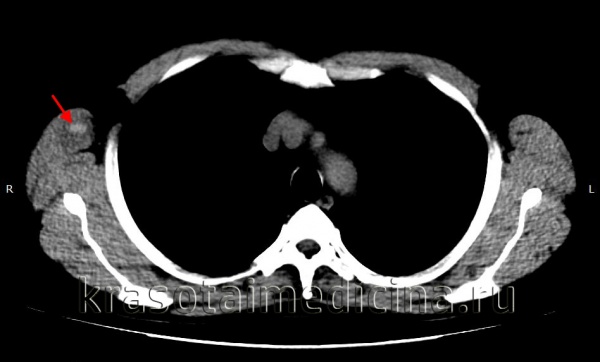

image

КТ ОГК. Гиперденсное скопление крови в толще мышечного массива грудной стенки справа, окруженное зоной отека.